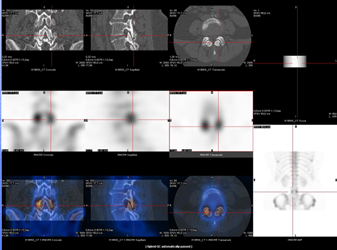

Si, dans le cancer du sein, l’imagerie planaire est souvent suffisante pour déterminer de façon précise la localisation anatomique du ganglion sentinelle, la situation peut être plus délicate dans les cas de mélanomes où le site de drainage lymphatique n’est pas toujours évident et les régions anatomiques complexes. Le SPECT/CT permet alors d’augmenter la précision anatomique en indiquant la profondeur et la localisation précise du ganglion sentinelle.  La connaissance pré-opératoire précise de la localisation anatomique permet de faciliter le geste chirurgical consistant à extraire le ganglion sentinelle pour analyse et de planifier la voie d’abord (fig. 5).

Figure 5 - Cancer du sein : ganglion sentinelle localisé par SPECT/CT